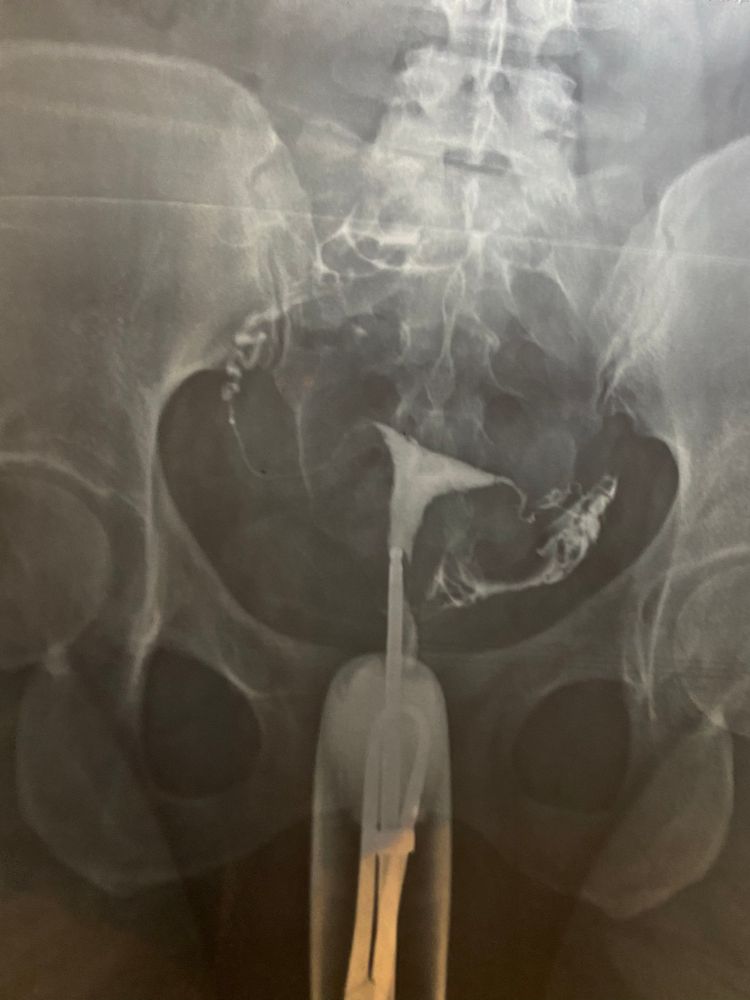

мне по узи труб непроходимость ставили, а по ренгену проходимы! но вот на рентгене вроде у меня прям потолще трубы! Автор а сколько вы уже планируете?

Я когда делала ГСГ, мне вообще сказали, что трубы не проходимы, что мол надо сразу их удалять и на эко. В итоге лапара показала, что с трубами все отлично. Потом беременела сама.

Челябинск ГСГ Проходимость маточных труб